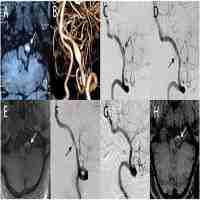

| Abstract | OBJECT: Use of a flow-diverting device has shown promising short-term results in the management of vertebral artery (VA) dissecting aneurysms, but there is still uncertainty regarding its long-term efficacy and safety. The authors report their initial experience with respect to the potential utility and long-term clinical outcomes of using a flow-diverting device in the treatment of unruptured dissecting VA aneurysms. METHODS: The authors conducted a retrospective review of all cases of unruptured intracranial VA dissecting aneurysms treated at their institution (Tuen Mun Hospital) with a flow-diverting device. They describe the clinical presentations and angiographic features of the cases and report the clinical outcome (with modified Rankin Scale [mRS] scores) at most recent follow-up, as well as results of the latest angiographic assessment, with particular focus on in-stent patency and side-branch occlusion. RESULTS: A total of 4 aneurysms were successfully obliterated by using flow-diverting devices alone. Two devices were deployed in a telescoping fashion in each of 2 aneurysms, whereas only 1 device was inserted in each of the other 2 aneurysms. No periprocedural complication was encountered. No patient showed any angiographic evidence of recurrence, in-stent thrombosis, or side-branch occlusion in angiographic reassessment at a mean of 22 months after treatment (range 18-24 months). As of the most recent clinical follow-up (mean 30 months after treatment, range 24-37 months), all patients had favorable outcomes (mRS Score 0). CONCLUSIONS: Reconstruction using a flow-diverting device is an attractive alternative in definitive treatment of dissecting VA aneurysms, demonstrating favorable long-term clinical and angiographic outcomes and the ability to maintain parent artery and side-branch patency. It is particularly useful in cases with eloquent side-branch or dominant VA involvement. |